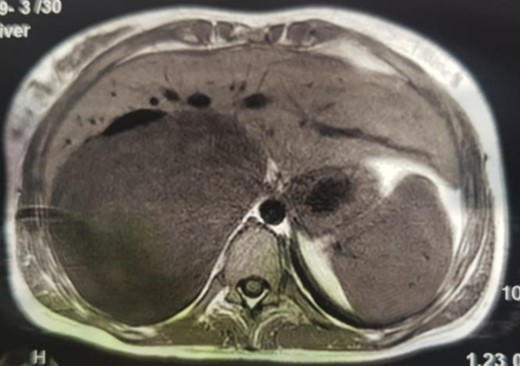

An MRI angiogram to assess the vascular relationships of the tumor revealed a 125 × 110 × 95 mm3 well-bounded, oval, slightly heterogeneous right adrenal mass with a mixed T2 signal and hypointense T1 signal. Angiographic sequences showed no portal venous thrombosis; the lesion was adherent to the right liver and the inferior vena cava (IVC), which was compressed but remained permeable, and came into contact with the superior mesenteric artery and the superior mesenteric vein, which were also permeable. The hepatic pedicle was also slightly pushed forward (Figs. 2 and 3).

MRI, well-limited oval right adrenal mass, slightly heterogeneous mixed T2 signal (arrow: aorta; arrowhead: compressed IVC).

MRI, voluminous lesion of the right adrenal medulla in hyposignal T1.